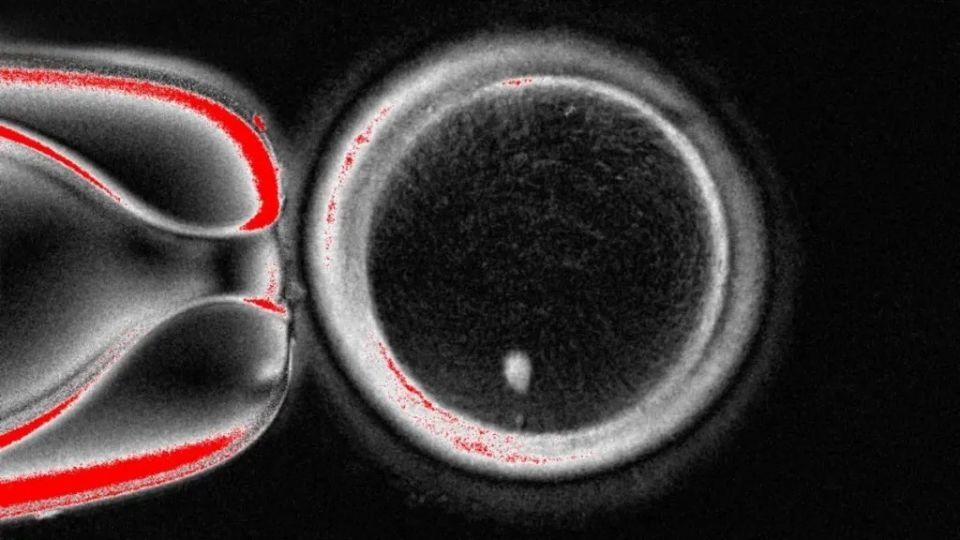

Ο μεγάλος κύκλος είναι το ωάριο όπως φαίνεται στο μικροσκόπιο, και η λευκή τελεία στο κάτω μέρος του είναι το γενετικό υλικό που αντλήθηκε από δερματικό κύτταρο και τοποθετήθηκε μέσα στο ωάριο

OHSUΩστόσο, το ωάριο περιέχει ήδη το πλήρες σετ των 46 χρωμοσωμάτων, κάτι που καθιστά αδύνατη τη γονιμοποίηση. Το επόμενο στάδιο ήταν να «πείσουν» το ωάριο να απορρίψει το ήμισυ των χρωμοσωμάτων του – μια διαδικασία που οι ερευνητές έχουν ονομάσει «μιτομείωση» – ώστε να φτάσει στα 23, όπως συμβαίνει φυσιολογικά στην αναπαραγωγή.